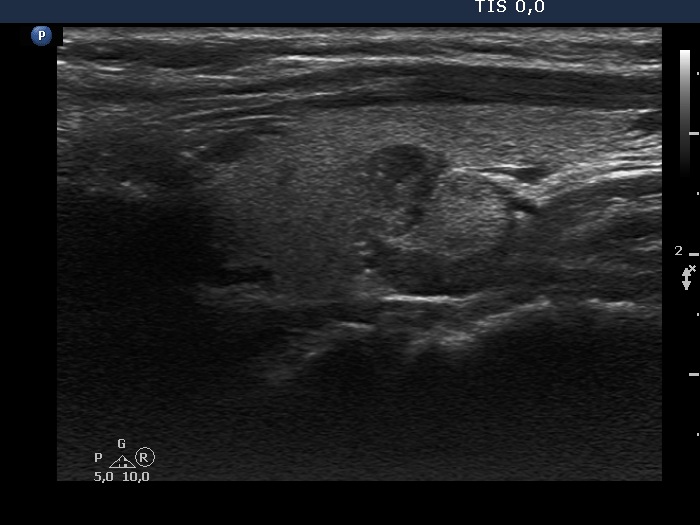

The borders of the nodule - case 2115 |

Clinical presentation: A 42-yr-old woman was referred for evaluation of a nodular goiter detected by chance on carotid Doppler examination.

Ultrasonography. The thyroid was echonormal. There was a mass in the dorsal part of the left lobe. The lesion presented parts with different echogenicities.

Comment. The issue is whether the lesion is composed of one or more nodules. In the former case it has lobulated margins, in the latter this is a non-pathological lobulation. Nonetheless, the question is only theoretical because the nodule requires cytological evaluation.